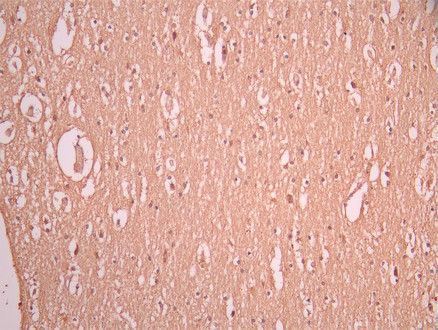

IHC image of CSB-RA916692A0HU diluted at 1:100 and staining in paraffin-embedded human brain tissue performed on a Leica BondTM system. After dewaxing and hydration, antigen retrieval was mediated by high pressure in a citrate buffer (pH 6.0). Section was blocked with 10% normal goat serum 30min at RT. Then primary antibody (1% BSA) was incubated at 4°C overnight. The primary is detected by a Goat anti-rabbit polymer IgG labeled by HRP and visualized using 0.05% DAB.